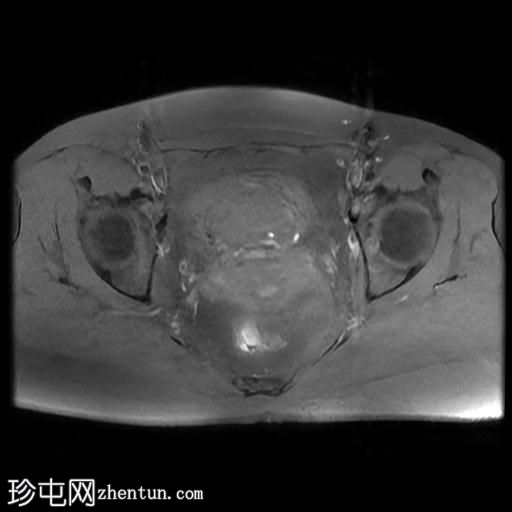

MRI

轴位

T2加权像

盆腔MRI显示双侧子宫旁多条迂曲静脉,自子宫肌层延伸至盆腔。

此外,左侧附件可见两个充满液体的单纯性囊肿,大小分别约为31 mm和32 mm;右侧附件可见一个卵泡囊肿,大小约为19 mm。

影像学特征符合盆腔充血综合征的诊断,患者为35岁女性,有慢性盆腔疼痛和痛经病史。